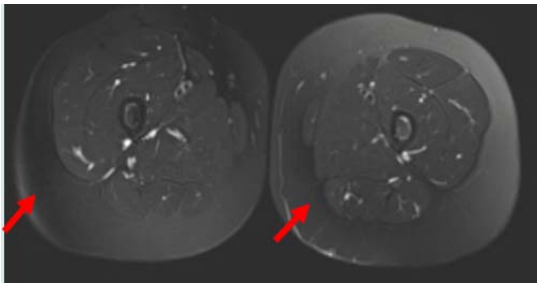

52.下肢MRI檢查時發生箭號所指之假影,最可能的原因為何?

(A)截斷假影(truncation artifact) (B)脂肪訊號抑制(fat suppression)不均勻 (C)化學位移假影(chemical shift artifact) (D)磁矩轉換(magnetization transfer)假影